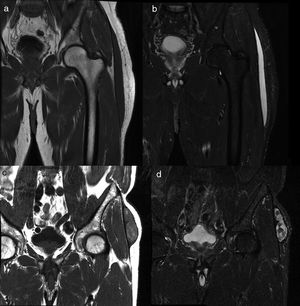

When the MRI was conducted, the lesions were described as type I or type III. All type I lesions were acute, while type III lesions were chronic (Fig. 4).

MRI findings on the MLL. Subacute MLL (a,b). Thirty-three-year-old patient weeks after falling from the bicycle. Images on the coronal plane focused on the left trochanteric region of T1-weighted sequences (a) and T2-weighted sequences with fat suppression (b) on the coronal plane. Most subacute MLLs, as it is the case here, have cystic appearance. Chronic MLL (c,d). Seventy-four-year old patient without known prior trauma. Images on the coronal plane focused on the trochanteric region. Lesion of mixed and heterogeneous signal intensity on T1-weighted sequences (c) and T2-weighted sequences with fat suppression (d). MLL: Morel-Lavallée lesion.